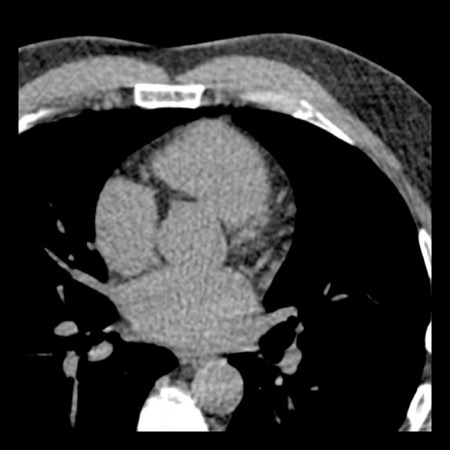

case 2 – CAD-RADS 5/P2/S

First, scroll through the CTA images.

How would you describe the findings on the coronary CTA?

The findings are:

- Stent in the mid

LAD with low-attenuation within the stent suggestive of minimal in-stent

restenosis (<25%). Non-calcified plaque distal to the stent

causing mild stenosis (25-49%). Notice bridging on a short segment in

the distal LAD. - Non-calcified

plaque in the LCX causing mild stenosis (25-49%). - Occlusion of the

proximal OM1 branch with distal filling. - Calcified and

non-calcified plaques in the proximal RCA causing mild (25-49%) stenosis. - Total plaque burden

is moderate based on SIS (four segments including proximal RCA, mid LAD, prox

LCX and OM1).

Due to the occlusion of OM1 branch and presence of the stent, this case

reads as CAD-RADS 5/P2/S, which means that this patient needs further

diagnostic workup.